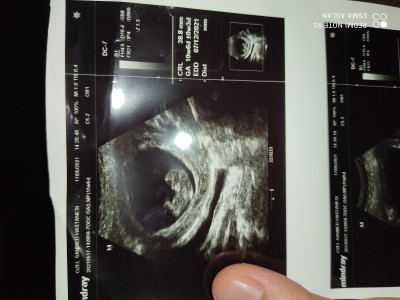

Kızlar varmı bebisi böyle olupta cinsiyetini öğrenen..

image

10+5 sanırım bebek. Böyleyken bir şey demek çok zor 12. haftada cinsiyeti belli olmaya başlar canım :)

13 haftalık canım

Ben kenarda 10w5d yi görünce yeni sandım kız ne bileyim :)) Allah hayırlı evlat etsin inşallah ♥️ bana biraz kız gibi geldi.

Kesesi yuvarlak olunca kız diyorlar genelde:)

Daha cok kucuk tahmin icin. Ben anlamam acikcasi keseden falan. Rabbim gonlunuze gore versin